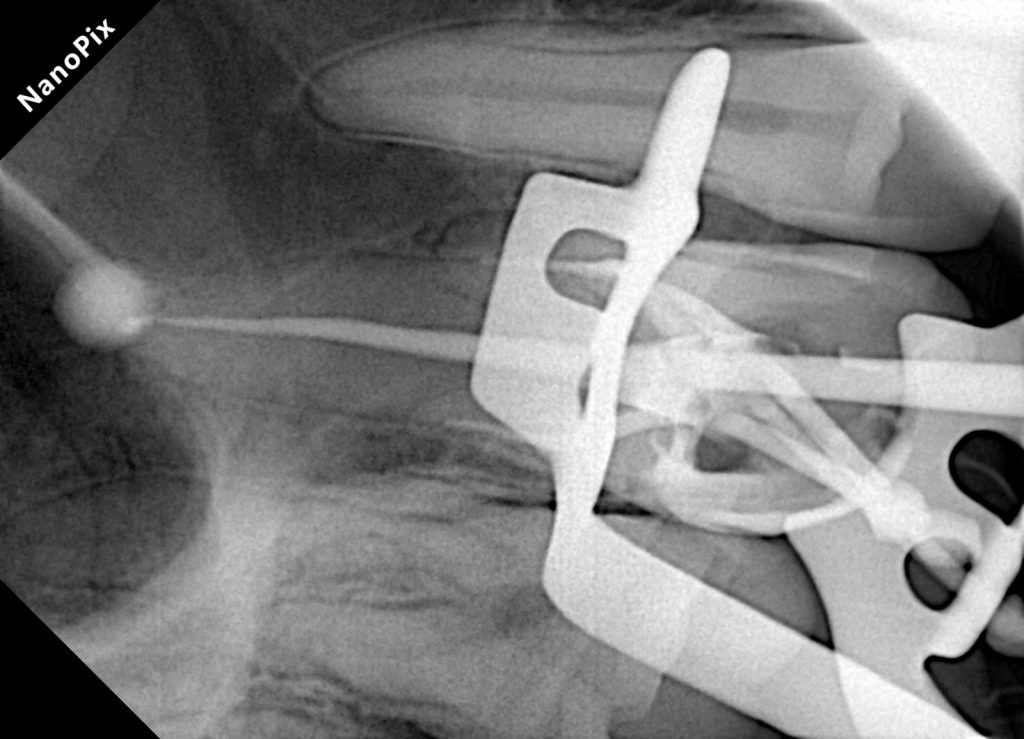

Canal Negotiation and Shaping

Canal orifices were identified under magnification. Glide path preparation and rotary instrumentation were carried out following a crown-down philosophy, maintaining original canal anatomy. Copious irrigation was performed using sodium hypochlorite with activation to enhance debridement.

Obturation

Following drying of the canals, obturation was completed using gutta-percha with a bioceramic sealer to ensure a three-dimensional seal. A postoperative radiograph confirmed adequate length, density, and taper of the root fillings.